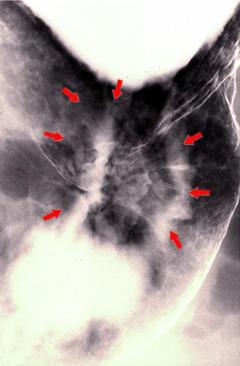

정면상으로는 표면함몰형(IIc형) 조기위암과 유사한 궤양침윤형(3형) 진행위암

[Image-ID:1424]

악성 상피성종양/선암

위(부위)/체부

X-P

3형(궤양침윤형)/

40이상

s(a)